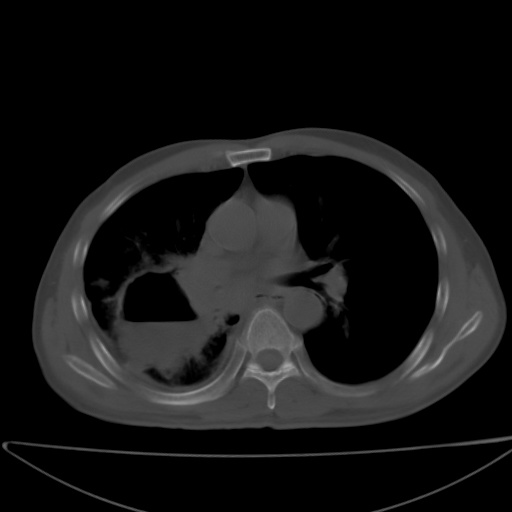

以下是引用jsgdoctor在2008-11-6 22:12:00的发言:[br]右主支气管壁明显增厚,管腔狭窄.考虑为右侧中央型肺癌伴阻塞性炎症\\肺脓肿.

以下是引用zjzjr在2008-11-6 20:25:00的发言:[br]中心型肺ca,合并阻塞性肺炎

以下是引用zsl6918在2008-11-6 19:43:00的发言:[br]右侧中心性肺癌(鳞癌)